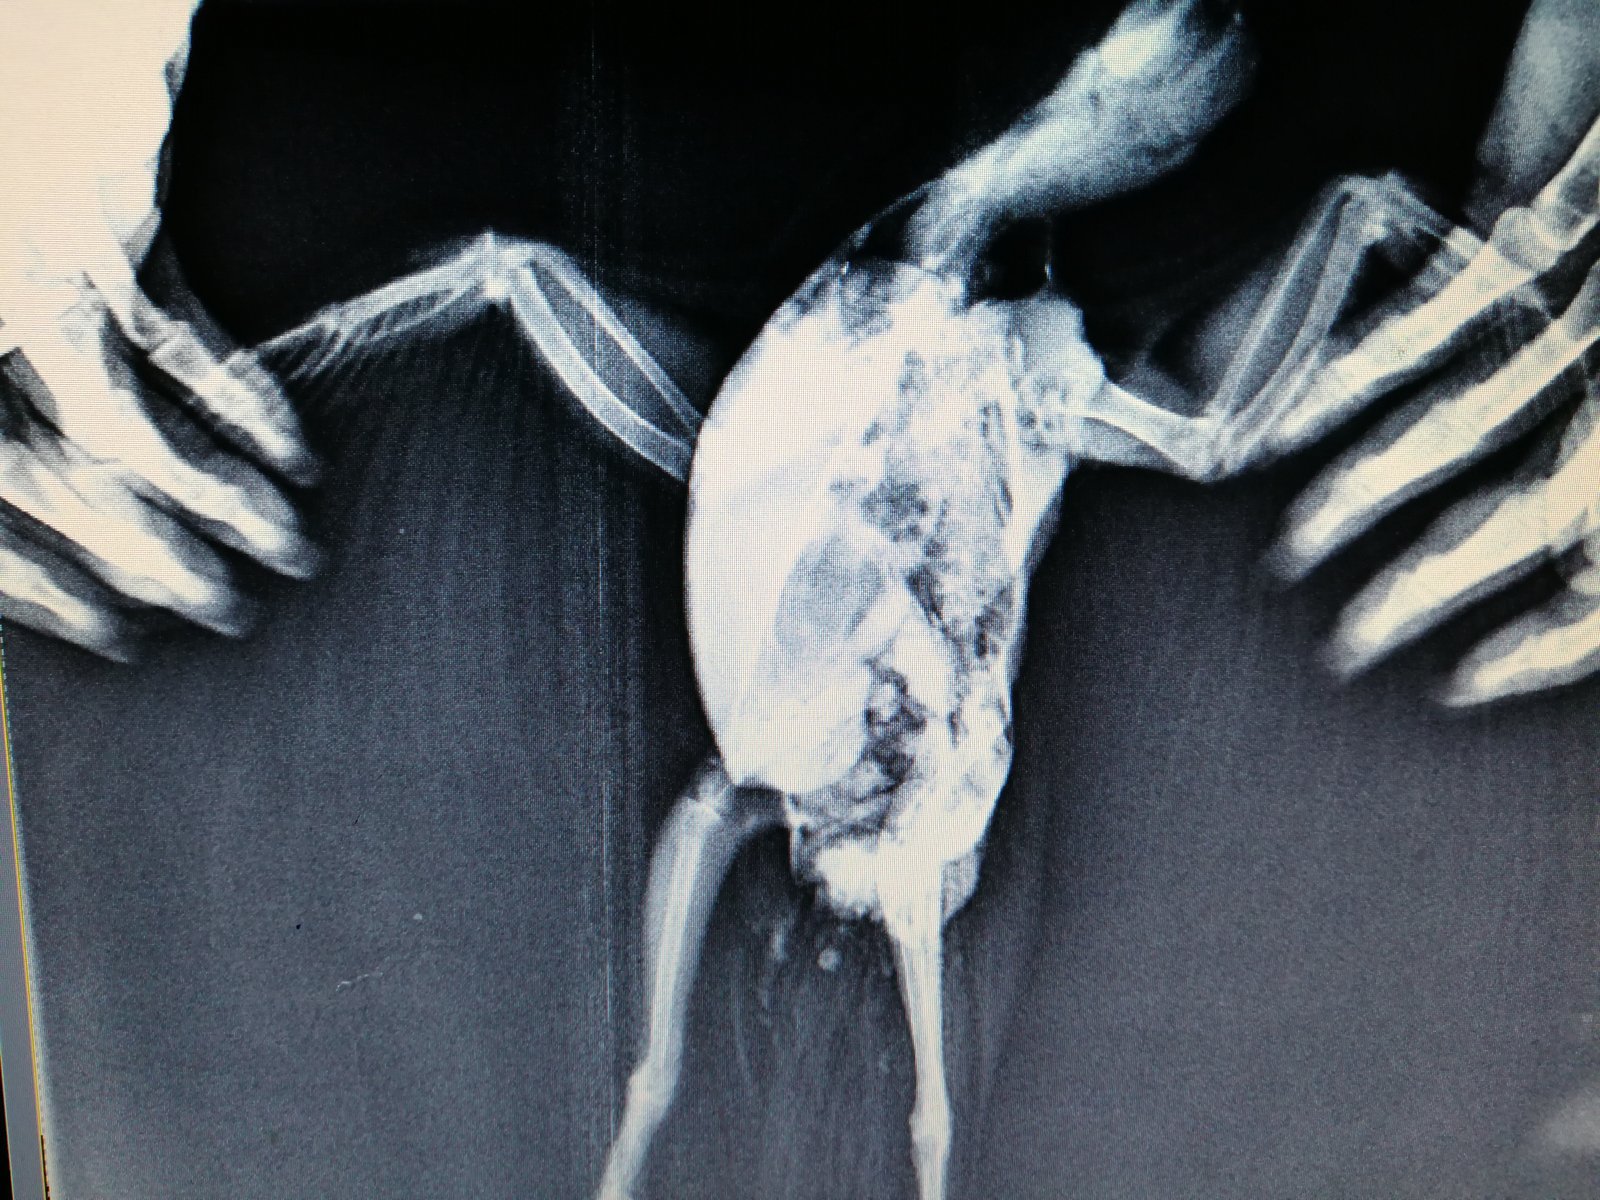

Elena1811 Опубликовано 7 марта, 2020 Автор #113 Опубликовано 7 марта, 2020 Мы старались как могли. Не получается его развернуть полностью из-за левого крыла. Не разворачивается доконца. Боялись сломать

Zosia Опубликовано 7 марта, 2020 #124 Опубликовано 7 марта, 2020 Если есть файлы на флешке- то мне на почту киньте. Т.к. в переснятом виде снимки нечитабельны. zofia68@mail.ru

Elena1811 Опубликовано 11 марта, 2020 Автор #130 Опубликовано 11 марта, 2020 Получила ответ от Зофии. Нужны разъяснения. И некоторые препараты я не могу купить Вот что пишет Зофия: Ну, отличить голубя от голубки я по фото не смогу. Хотя ИМЪО мне видится голубка. И те новообразования в брюшной полости (которые могцт передавливать нервные окончания, идущие к лапкам)- характерны именно для голубок, у меня даже фото есть гранулем, которые у них «рождаются» вместо яиц. Так что ИМХО- итраконазол в дозе 15 мг/кг каждые 12 чсов, нисиатин в дозе 75 000 ед в сутки на 100 гр веса, преднизолон из арсчета 3 мг/кг в сутки. Первый курс- 21 день. Для прикрытия преднизолона- Деринат капли назальные, принимать орально 4 капли в сутки весь курс. Обязательно гепатовте- 0,2-0,3 мл в сутки. По крылу- ваш снимок не дает возможности оценить фатальность нарушений. Но скорее всего- там уже вряд ли что можно сделать (и по-любому это вопрос-не вопрос жизни). ......... У нас беда с преобретением лекарств, рецепты только лишь на аналгин не нужны..